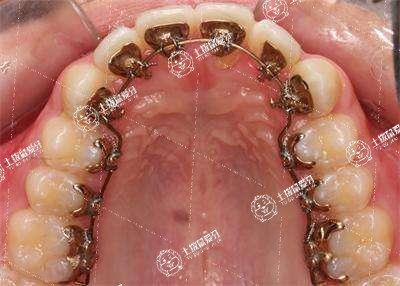

3.反頜會影響到美觀,還會影響到牙齒的健康,應(yīng)該要積極的進(jìn)行矯正,主要是使用矯治器進(jìn)行矯正,如果存在一些骨性反頜,通過矯正器治療效果不明顯,必要的時候還需要進(jìn)行正畸正頜聯(lián)合治療。

地包天的糾正主要是取決于骨性或是牙性的原因,不同性質(zhì)的地包天治療方法也會有所不同,然而采取牙齒矯正器就可以取得良好的治療效果。

地包天牙齒矯正需要3個月到3年左右。乳牙期形成反頜時,可以在2~3歲佩戴活動矯治器推動上前牙唇向移動,抑制下頜前伸,解除反頜,約需3~6個月。乳恒牙替換完畢,10~14歲可以佩戴固定或隱形矯治器壓低下前牙,唇向擴(kuò)展上前牙,促進(jìn)牙槽骨發(fā)生生長改建,形成淺覆頜淺覆蓋的咬合關(guān)系,約需1~2年。如果發(fā)生骨性反頜,還要進(jìn)行整頜外科手術(shù),截除過長的下頜骨,約需3年左右。矯正結(jié)束后要堅持佩戴保持器,防止復(fù)發(fā)。